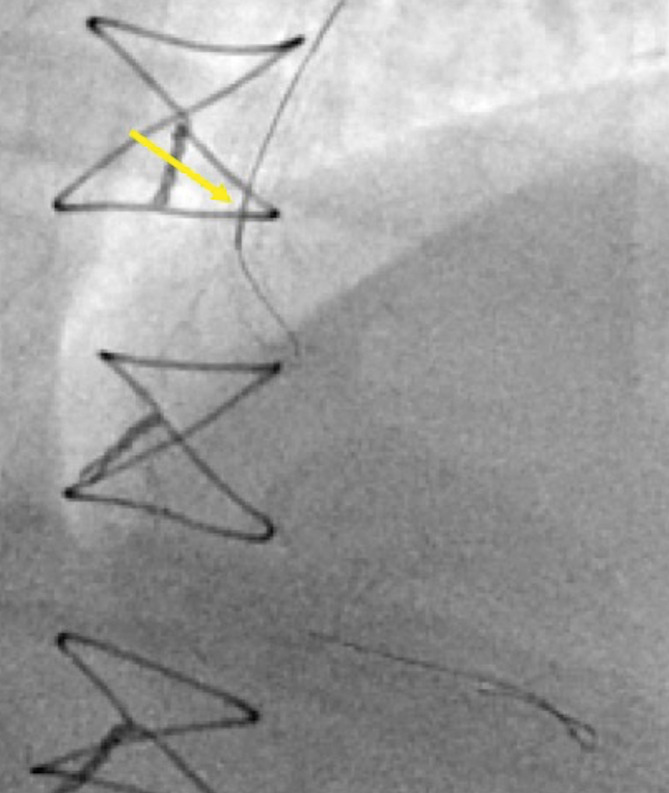

6c. DK Crush(Double Kissing Crush)

DK Crush 是目前證據最充分的 2-stent 分叉病灶治療技術

被 network meta-analysis 評為所有 2-stent 技術中排名第一

DK Crush 11-step overview

Figure 6. DK Crush 完整 11 步驟總覽(Hall et al., EuroIntervention 2021)。此為本教學文件最重要的圖片。

DK crush technique illustration

Figure 7. DK crush technique 示意圖。

DK Crush 完整 11 步驟

1. Wire MV and SB:送導絲至 MV 與 SB。

2. Balloon predilate MV and SB:充分的病灶準備(lesion preparation)。對 MV 與 SB 分別以 balloon 預擴張。

3. SB stent deployment + MV balloon positioning:在 SB 放置支架,使其突出 MV 約 2 mm。同時在 MV 預先放置 balloon(位於 SB stent 突出處)。

Tip: SB stent 先以 nominal pressure 釋放,退出 balloon 後再以高壓充氣確保完整貼壁。

4. Balloon crush:充氣 MV balloon,將 SB stent 的突出部分壓碎貼壁至 MV 壁。

5. Re-wire SB through PROXIMAL strut:移除舊的 SB wire,從 proximal strut 重新送導絲進入 SB。

6. 1st Kissing Balloon Inflation(1st KBI):這是 DK crush 的核心創新步驟。在 MV stent 放置之前就進行第一次 kissing balloon,清除被壓碎的 SB stent struts 對 SB ostium 的阻塞。

7. MV stent deployment:在 MV 放置支架(此時可移除 SB wire)。

8. POT:以 NC balloon(1:1 sized to proximal MV)進行 proximal optimization。

9. Re-wire SB:再次從 proximal strut 送導絲進入 SB。

10. Final Kissing Balloon Inflation(FKBI):第二次 kissing balloon。

11. Re-POT:最後再做一次 POT,矯正 KBI 造成的 proximal MV 橢圓形變形。

⚠ DK Crush 的關鍵技術要點

• Proximal strut rewiring 是 CRITICAL:不同於 culotte(走 distal strut),DK crush 必須從 proximal strut 進行 rewiring。從 proximal strut 進入可以確保 wire 不會被卡在壓碎的金屬層之間。

• 1st KBI 是 DK crush 的關鍵創新:先做一次 KBI 清除被壓碎的 struts,使後續的 FKBI 成功率提升至 100%(vs classic crush 的 75%)。

• POT 使用 NC balloon,大小以 1:1 對應 proximal MV 管徑。

• KBI 技巧:使用短球囊(short balloon),先 sequential high-pressure inflation 各分支,再 simultaneous low-pressure inflation。